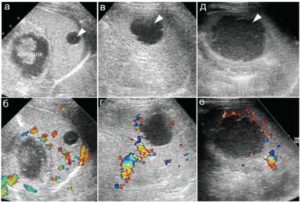

Обнаружить небольшие кисты у новорожденных помочь может только УЗИ – пальпация образование не выявит, симптомов может не быть совсем, а ребенок не в состоянии сказать, где именно ощущается дискомфорт (даже если он есть).

Помимо ультразвукового исследования, применяется:

- КТ – позволяет уточнить локализацию, установить (не на 100%,) тип полости – истинная, ложная или паразитарная, оценить состояние сосудов селезенки, оттесненных опухолью, исключить злокачественный процесс;

По мере лечения проводится контроль динамики опухоли при помощи УЗИ.

Лечебная терапия, если диагностирована киста селезенки у ребенка, назначается только после проведения комплексной диагностики. Диагноз ставится на основании данных анамнеза, по результатам УЗИ.

Проводится компьютерная томография, МРТ, ряд лабораторных анализов, аллергические пробы.

Контроль динамики кисты при медикаментозном лечении проводится регулярно с помощью УЗИ.